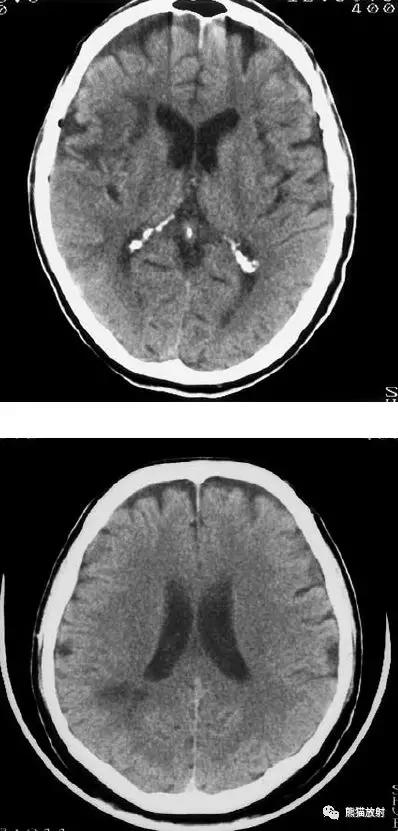

右侧大脑中动脉区域脑梗死,脑回样强化。

左侧额叶脑梗死(发病后12d),由于模糊效应平扫显示不清,增强扫描脑回样强化。

右侧基底节区脑梗死,增强后病灶看上去有所缩小。